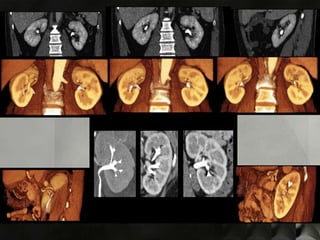

Urografia excretora